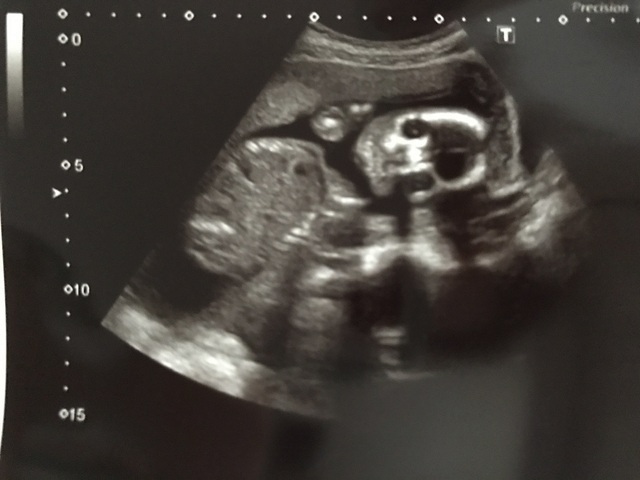

20週1日(20w1d・性別不明)|たらち さん(33歳)

エコー写真撮影時のエピソード:

旦那さんが初めて立ち会ったエコーで、かわいい姿や性別が分かるドキドキの瞬間でしたが、断面図のエコーが主だったようで、ガイコツ風のリアルな画像しか見れず、性別も分からずで、残念でした。。。

旦那さんの感想は怖いの一言でした(苦笑)